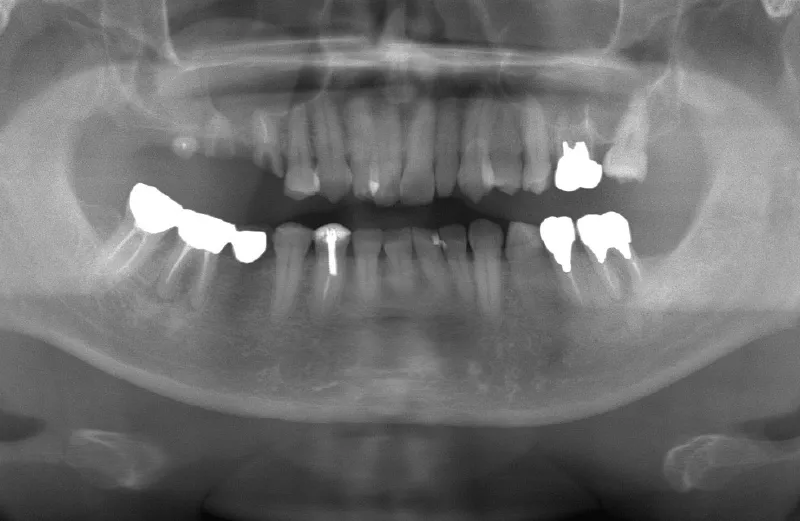

メガジェンオペの症例紹介04

治療前

治療後

| 主訴 | 他院では左上6左下6右上567の根が割れているのと、虫歯が深く保存できないと言われた。 残っている骨の状態が悪く、上顎洞までの垂直骨量が不足しているので抜歯後しばらく待ってからサイナスリフトが必須であり、インプラント治療に1.5年かかると言われたのでセカンドオピニオンを希望で来院。入れ歯は嫌でどうにか短期間で噛めるようにインプラントでの治療を希望している。 |

| 治療期間 | 2.5ヶ月で仮歯が入り、 4ヶ月で最終補綴物が入って終了。 |

| 治療費 | 約2,000,000円 |

| 治療内容 | 上顎にはエクストラワイドショートインプラントを埋入し、上顎洞を移植材を用いずに挙上しインプラントを埋入した。約2.5ヶ月で仮歯を装着し、様々な機能面に問題がないことを確認し4ヶ月で最終補綴物を装着して終了した。 |

| 治療の リスク |

インプラント埋入オペ時に術者が上顎洞内にインプラントを迷入させる可能性がある。これは術者が技術的に熟練していれば防ぐことが可能。 |